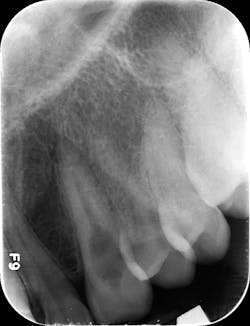

CBCT imaging or taking angled radiographs can help determine which type of resorptive process is being presented. Periapical radiographs are not great at giving you an accurate picture of the lesion’s size,4 but if you discover a possible resorption lesion upon clinical examination, you can use a periapical radiograph to determine if the lesion is indeed external or internal.

Start by taking a baseline radiograph of the lesion using a paralleling technique and a beam-aiming device, such as a Rinn instrument. With your second periapical radiograph, make a mesial horizontal shift with the tube head. If the process is on the tooth’s external surface, the resorptive lesion will move as the radiograph is shifted. Internal resorptive processes will always stay centered in the tooth when the angle is changed (figure 2). With external resorption, one canFinding a “pink spot” during an exam can be a little disheartening. Clinicians never like to deliver bad news or have to prepare a patient for a poor prognosis. Luckily, the incidence of both of these conditions is low; however, early diagnosis and treatment are always best to ensure your patients’ health and retention of their teeth. Cheers!